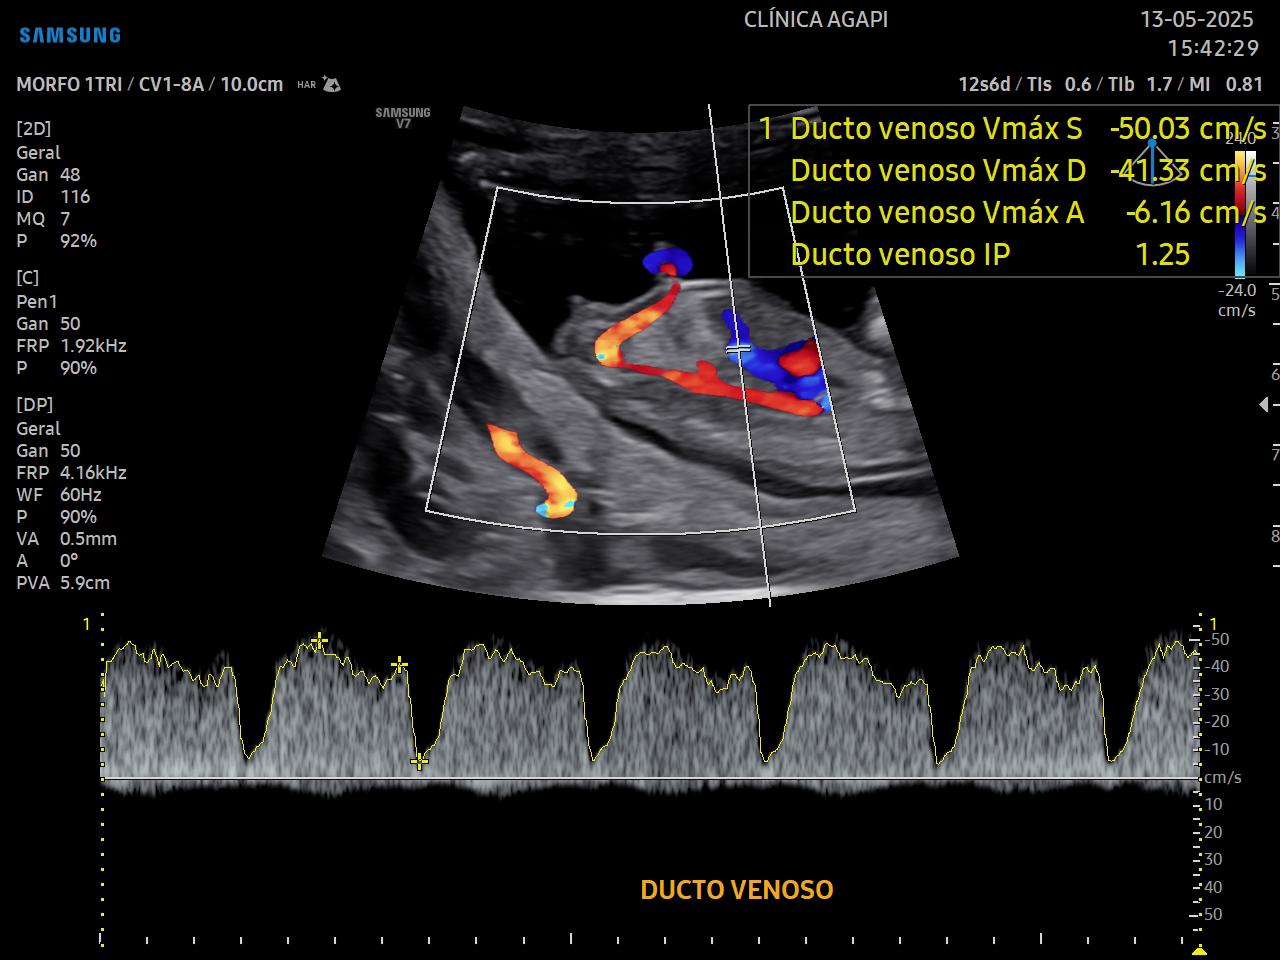

O rastreio de aneuploidias é feito através da avaliação de marcadores ultrassonográficos específicos como: transluscência nucal, osso nasal, ducto venoso e regurgitação tricúspide.